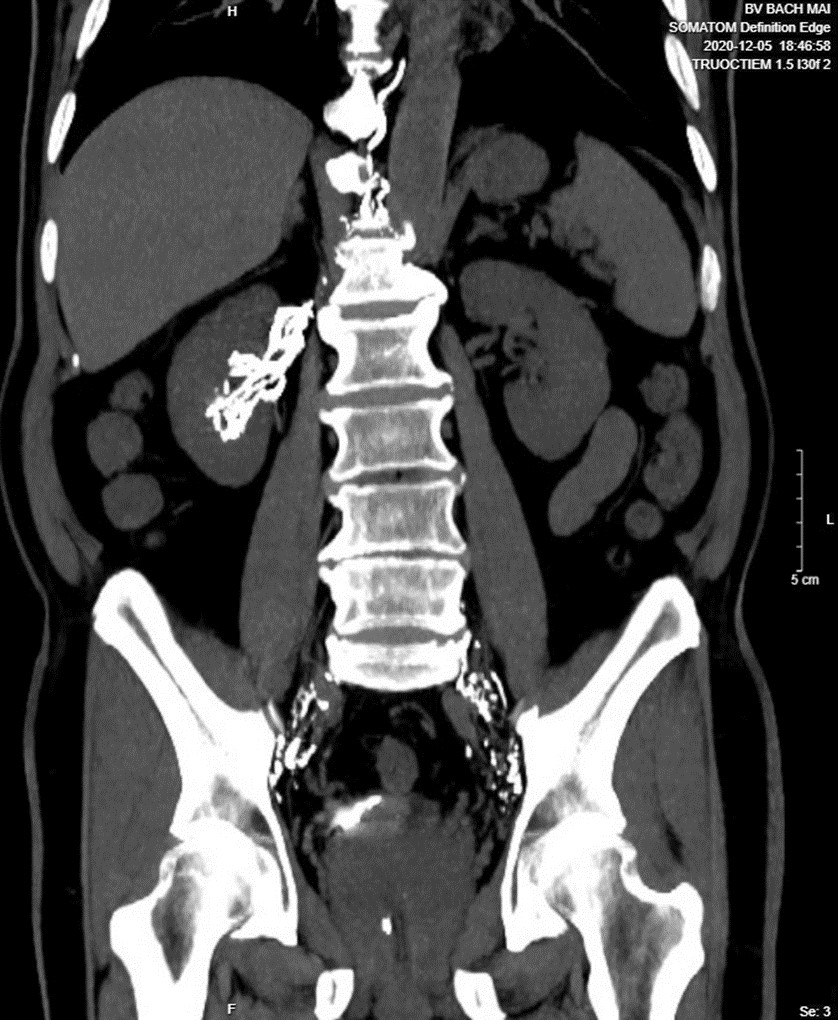

Ảnh 4. Chụp CT sau chụp DSA cùng bệnh nhân, thấy bạch mạch sau phúc mạc, bể dưỡng chấp và ống ngực. Lipiodol trong bạch mạch trung thất

| Ảnh 6 và 7. Chụp CT sau DSA thấy lipiodol từ bạch mạch sau phúc mạc đi vào thận phải và vào đài bể thận phải, qua niệu quản rồi xuống bàng quang. Đái dưỡng chấp là do rò bạch mạch bể thận phải. |